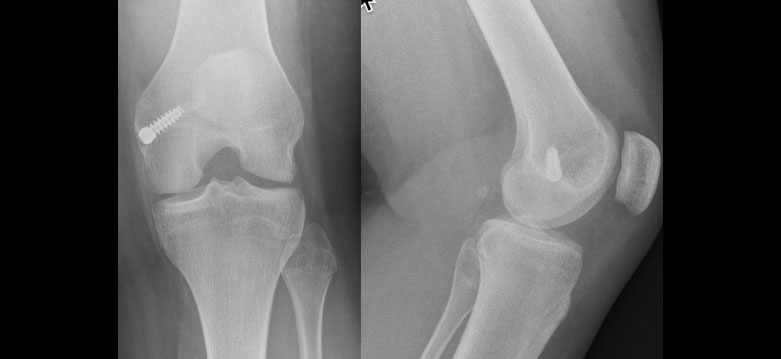

This case demonstrates on XR the left hip in a “frog leg lateral” (right side your screen) demonstrated the subtle signs of a slipped epiphysis.

This adolescent had both hips pinned. There is discrepancy of opinion between surgeons whether both sides should be pinned initially, or whether to only operate on the second hip if symptomatic. Advances that have been made are using a different entry point to ensure the screw is aimed for the centre of the head, the operation might be done through a 1cm incision, and where possible stainless screws are easier to subsequently remove. The screw need not be removed as a rule.